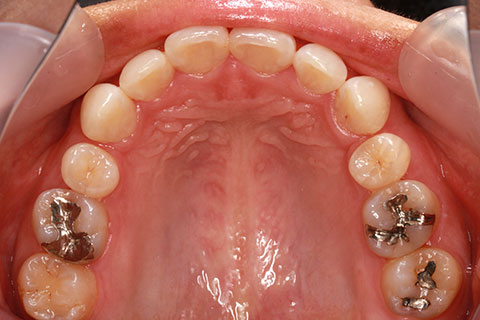

治療前

治療中

治療後

- 年齢・性別

- 23歳女性

- 治療期間

- 1年6ヶ月

- 抜歯

- 上顎4番

- 治療費

- 110万円(税込み)

- 備考

- ハーフリンガル矯正

- 治療内容

- 上下前歯部凸凹の改善

- 施術の副作用(リスク)

- 裏側矯正の特性上、表側矯正と比較すると治療期間が長くかかる場合が多い。